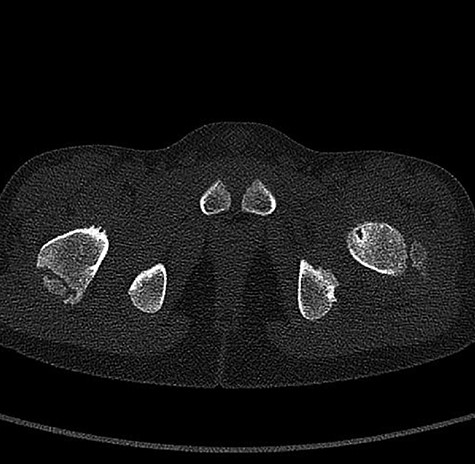

CT hips reported a well-defined lesion seen bilaterally in the neck of femur anterior infero-medial aspect, more prominent on the left side measuring 7 x 3 mm on left side both in coronal (Fig. 3) and axial (Fig. 4) views. On the right side, other lesion measuring 2 x 1 mm (Fig. 5) seen in coronal view. These two lesions are well defined with a sclerotic border with a small cortical defect. The lesion shows fat density. The symmetrical appearance of the lesion combined with the fat density and location suggest the diagnosis of synovial herniation pit. MRI Pelvis revealed minimal left hip joint effusion with loculated fluid seen along the trochanteric bursa with the largest measuring 0.9 x 1.5 cm (Fig. 6, 7).

Showed axial cut of CT hips demonstrating the synovial pit on left and right side.